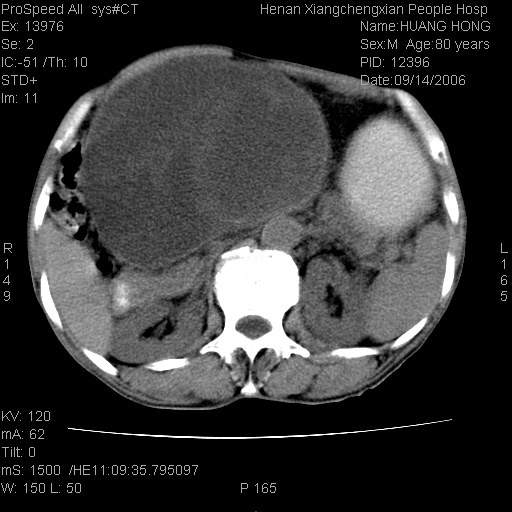

患者, 男, 80岁, 发现上腹部包块1年余,无其它不适.2006-9-14ct片是喝水后扫描2006-9-15ct片没喝水扫描![]() ![]() ![]() ![]() ![]() ![]() ![]() ![]() ![]() ![]() ![]() ![]() ![]() ![]() ![]() ![]() 以上是喝水片 以下是空腹片 ![]() ![]() ![]() ![]() ![]() ![]() ![]() ![]() ![]() ![]() ![]() ![]() ct:胰腺前方、肝脏与胃之间可见巨大类圆形囊性低密度影,大小约152mmx145mmx118mm,上缘平t11椎体上缘,下缘平l3椎体下缘,密度均匀,ct值15hu,其内呈多房分隔,囊壁薄且光滑,边界清晰,周围组织及器官明显受压。肝脏实质内未见异常密度影,胆囊未见异常,胰腺密度未见异常,脾脏大小、形态及密度未见异常,腹膜后间隙未见肿大淋巴结影。 印象:胰腺前方、肝脏与胃之间巨大类圆形囊性低密度影.性质待定。多考虑:.肠系膜巨大囊肿。 守望可可西里发言:支持楼主,考虑肠系膜囊肿,多为小肠系膜。 ysxyy发言:我总觉得这个病人虽然很像肠系膜囊肿,但还是应该强化一下; 下面这几幅图里肿块和主动脉的关系不太清,不知能否除外血管性来源? ![]() ![]() ![]() 病理结果:横结肠系膜间叶瘤.部分区域间质细胞增生活跃. 病理图片 ![]() 良性间叶瘤:是指由两种或两种以上的间叶组织所构成的混合性肿瘤.肿瘤仅发生在腹膜后和肠系膜,.前者较后者多发.良性间叶瘤常发生在肾或四肢,腹膜后较少见,各年龄均可发病.女多与男,预后较好,但术后易复法. 恶性间叶瘤:由两种以上恶性间叶组织成分组成. 光镜:肿瘤由脂肪/血管/平滑肌构成. 原贴地址: http://www.radinet.com.cn/forum_view.asp?forum_id=4&view_id=16217 ok |